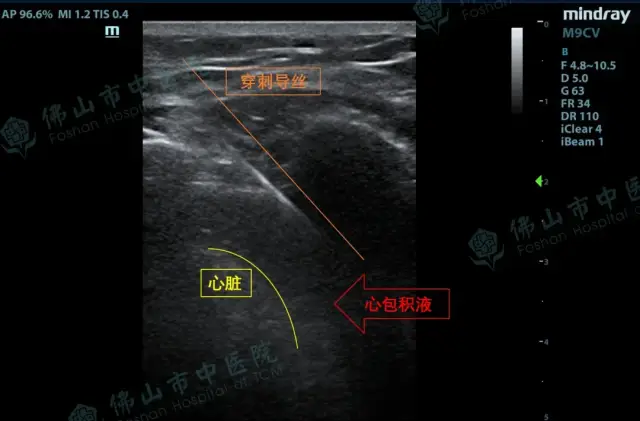

一针解压:超声引导精准穿刺,立竿见影

“真凶”锁定,ICU团队当机立断,即为患者施行超声引导下全程可视心包穿刺引流术。在重症超声的实时动态引导下,穿刺针精准避开重要结构,安全进入心包腔。随着积液被顺利引出,患者血压即刻显著回升至140/80mmHg,之前需要大剂量维持的血管活性药物得以全部撤停。患者血流动力学迅速稳定,转危为安。

超声全程直视下行心包穿刺